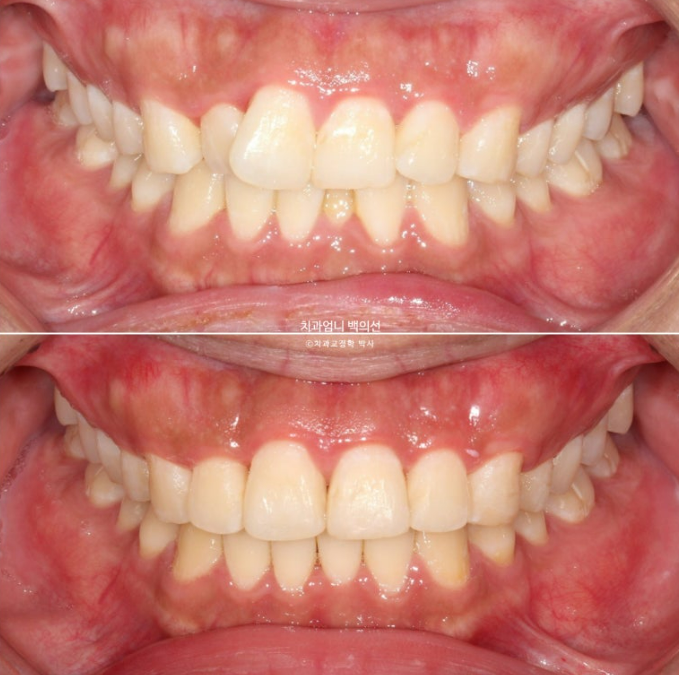

위가 치료 전 아래가 치료 후 예상 시뮬레이션 입니다.

파란 화살표 부위의 비스듬히 마모된 부분이 교정 전에는 티가 안나다가 배열이 완료가 되면 비로소 티가 많이 나게 되는거죠.

이런 경우 마모된 부분을 레진으로 수복하기 보다는 티가 덜나게끔 끝단을 조금 편평하게 다듬으면 좋습니다.

이제 전 후 비교 보겠습니다.

25.02~25.06